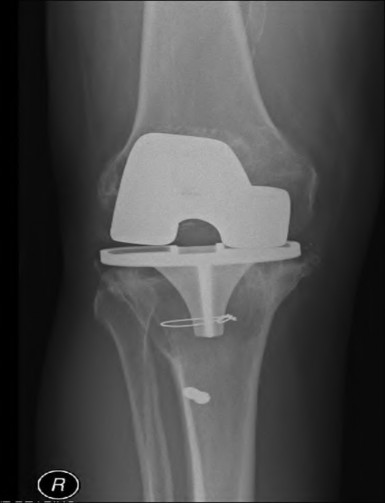

Question 40

During a complex revision TKA, the surgeon notes profound laxity and attenuation of the medial collateral ligament (MCL) such that the knee cannot be balanced coronally in either flexion or extension. The extensor mechanism and posterior capsule remain completely intact. Which level of prosthetic constraint is most appropriate in this scenario?